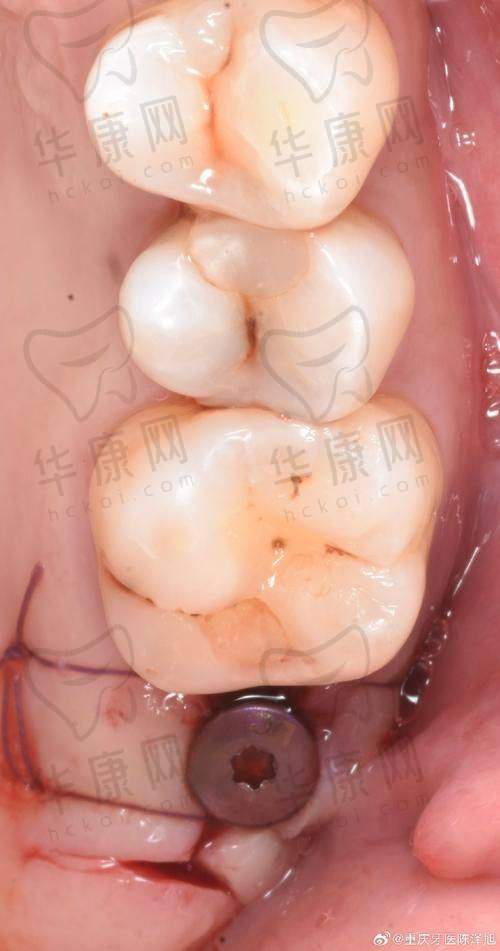

该口腔门诊部主打德系种植技术,在瑞士ITI种植牙方面有着独特的优势。其擅长即刻种植和微创种植技术。即刻种植技术可以在拔牙后立即进行种植,大大缩短了患者的治疗周期,减少了多次就诊的麻烦。而微创种植则是通过微小的切口进行种植手术,对患者的创伤小,术后修复快,患者在术后的疼痛感也相对较轻。比如,曾经有一位患者在溧水瑞齿固德口腔进行瑞士ITI种植牙,采用微创种植技术,术后当天就能正常饮食,修复速度超出了患者的预期。

医院拥有新型的设备,为瑞士ITI种植牙手术提供了精细的保护。精良的口腔CT设备可以清晰地显示患者口腔内部的结构,帮助医生更正确地了解患者的牙槽骨情况,从而制定出更合适的种植方案。在手术过程中,使用的种植器械也都是经过严格筛选的,确保手术的安心性和成功几率。例如,通过精良的设备,医生可以严谨地控制种植体的植入位置和角度,提高种植牙的稳定性和美观度。